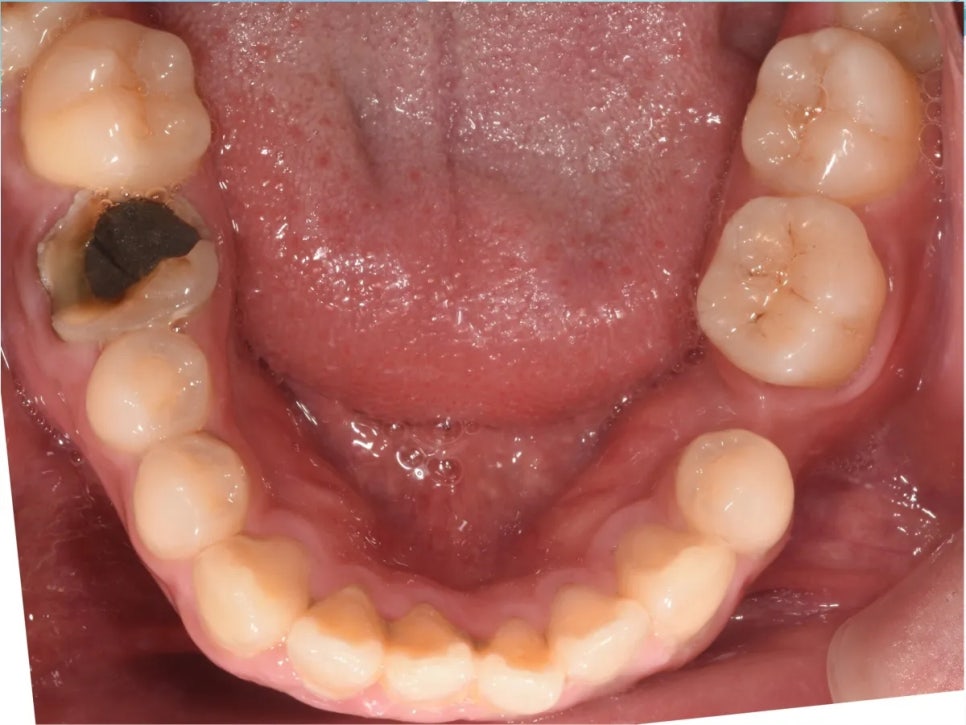

아래쪽 오른쪽에는 심한 충치, 반대쪽에는 이미 치아가 빠져 있는 상태

추가적으로, 아래쪽 오른쪽 첫째 어금니에는 심한 충치가 있었고, 반대쪽(왼쪽) 아래 두 번째 작은어금니는 이미 빠진 상태(결손)였습니다. 충치로 인해 치아 높이가 낮아지면서 위 어금니가 더 빨리 정출되었고, 결손 부위에서는 인접 치아가 빈 공간 쪽으로 쓰러져 있었습니다. 아래 사진을 보시면 이 모든 이유 때문에 결국 환자분이 아래턱을 틀어 물고 있는 것도 확인해보실 수 있습니다.